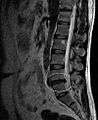

MRI scan of cervical disc herniation between fifth and sixth cervical vertebral bodies. Note that herniation between sixth and seventh cervical vertebral bodies is most common.

- Magnetic resonance imaging (MRI): A diagnostic test that produces three-dimensional images of body structures using powerful magnets and computer technology. It can show the spinal cord, nerve roots, and surrounding areas, as well as enlargement, degeneration, and tumors. It shows soft tissues even better than CAT scans. An MRI performed with a high magnetic field strength usually provides the most conclusive evidence for diagnosis of a disc herniation. T2-weighted images allow for clear visualization of protruded disc material in the spinal canal.